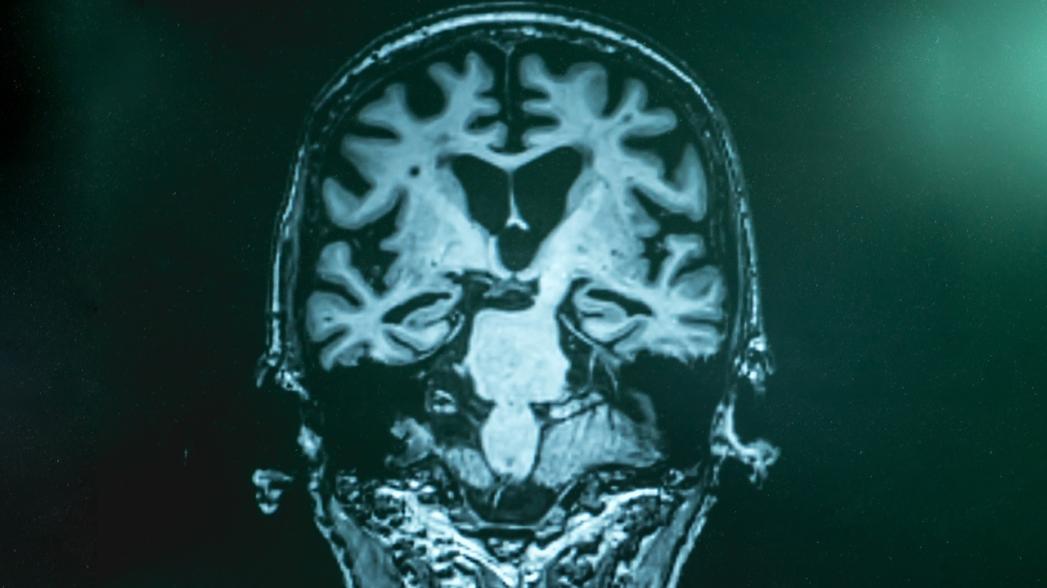

Новое исследование выявило патологическую активность мозга, которая предшествует симптомам болезни Альцгеймера за много лет - повышенная активность в гиппокампе во время анестезии и сна, возникающая в результате сбоя в механизме, стабилизирующем нейронную сеть.

Исследователи изучали гиппокампальную область мозга в животных моделях болезни Альцгеймера, измеряя активность клеток в гиппокампе, когда животные были бодрствующими и активными, а также когда они спали или находились под наркозом.

Несмотря на то, что известно, что активность нейронов гиппокампа снижается у спящих под наркозом здоровых животных, активность гиппокампа оставалась высокой у животных с болезнью Альцгеймера. Это связано со сбоем в физиологической регуляции, никогда ранее не наблюдавшимся в контексте болезни Альцгеймера.